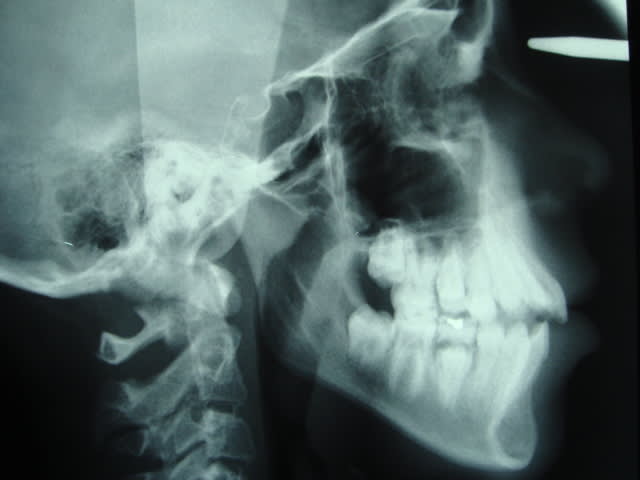

Elle est en déocclusion jusqu'aux 1er molaire, en classe 2 molaire, et un exces de recouvrement qui me ferai penser aussi aux extractions mais le profil ne risque-t-il pas d'être altéré?

C'est curieux ( mais ca arrive), d'apres le profil ostéo -dentaire, on ne serait pas attendu a un tel profil cutanné!!! Je reconnais ici que des extractions pM peuvent présenter un préjudice esthétique dabns e cas particulier

ANB est de combien , Go-GM francfort?

De toute facon il est claire que ce cas presente une dysfonction linguale et je ne sais pas si cela etait pris en charge par l'orthodontiste precedent ou pas, c'est un probleme qu'il faut regle. La chainette est dramatique pour l'hygiene et cela aussi doit etre pris en consideration. Un point tres important c'est de savoir si cette beance etait la avant de commencer ou s'est cree pendant le traitement et a quel moment. Personellement je trouve aussi que la solution proposee par le nouvel orthodontiste n'est pas la meilleure, je serai tente par une FEO occipitale ( appui vertical ) afin de reduire la classe II, redresser le plan occlusal et provoquer une autorotation de la mandibule ce qui va reduire la hauteure verticale anterieure et ameliore la musculature labiale et peri orale car sur la photo il y a une tension quand meme.. Ceci est mon avis a premier vu mais les radios peuvent confirmer ceci ou pas. Bon courage

Voici la tele que j'ai recupéré, la patiente a maintenant 14,5 ans. le traitement a commencé alors qu'elle avait 13 ans mais elle n'a pas suivi ces rendez-vous régulièrement.

Pour l'instant, une feo avec traction verticale pour avoir comme effet une bascule du maxillaire vers le bas serait souhaitable d'après vos réponses. Et pourquoi pas des élastiques d'intercuspidation et mécanique de classe 2 et pendant combien de temps?

Bref revenons au cas, d'apres la radio je trouve que la beance etait la avant de commencer et cela n'a pas ete pris en charge pendant la premiere partie du traitement!!! Donc il faut le faire maintenat au plus vite. La FEO a traction verticale c'etait mon idee et je la maintiens pour basculer le plan bispinal et favoriser une rotation anterieure de la mandibule ce qui corrige la classe II et reduit la beance. C'est une FEO de controle vertical du plan occlusal et non pas une force orthopedique. Il faut prendre les 7 aussi si cela n'a pas ete fait. Les elastiques de classe II dans une typologie aussi defavorable risque d'aggraver la tendance verticale et ce qu'on peut gagner sagittalement on le perd verticalement. A mon avis cela peut etre necessaire a la fin pour parfaire la classe I.